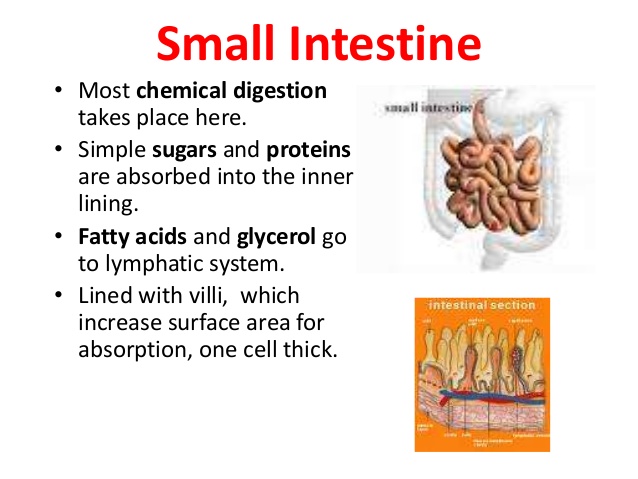

The small intestine is a long narrow tube which is long as 8 metres. The small intestine has 3 components.

(1) Duodenum

(2) Jejunum

(3) Ileum

Carbohydrates, proteins, fats and oil acidity is neutralized. Carbohydrates and proteins are turned into semi fluid called chyme while fats and oil are emulsified (changed to droplets).

Carbohydrates are finally digested into simple sugars and are absorbed into the blood stream and circulated. Proteins are finally digested from peptones into amino acids, absorbed and circulated. Emulsified fats and oil are digested into fatty acid and glycerol, absorbed into the blood stream and circulated.

The end products of digestion are simple sugars from carbohydrates, amino acids from proteins, fatty acids and glycerol from fats and oils. Vitamins, mineral salts and water do not need digestion. They exist in soluble and absorb-able forms. At the end of digestion, all the end products are absorbed in the small intestine through the Villi (singular: villus). The undigested food materials are passed into the large intestine.

The small intestine is a long narrow tube which is long as 8 metres. The small intestine has 3 components.

(1) Duodenum

(2) Jejunum

(3) Ileum

Carbohydrates, proteins, fats and oil acidity is neutralized. Carbohydrates and proteins are turned into semi fluid called chyme while fats and oil are emulsified (changed to droplets).

Carbohydrates are finally digested into simple sugars and are absorbed into the blood stream and circulated. Proteins are finally digested from peptones into amino acids, absorbed and circulated. Emulsified fats and oil are digested into fatty acid and glycerol, absorbed into the blood stream and circulated.

The end products of digestion are simple sugars from carbohydrates, amino acids from proteins, fatty acids and glycerol from fats and oils. Vitamins, mineral salts and water do not need digestion. They exist in soluble and absorb-able forms. At the end of digestion, all the end products are absorbed in the small intestine through the Villi (singular: villus). The undigested food materials are passed into the large intestine.